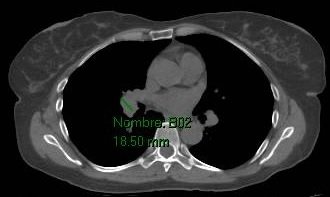

Se realizó radiografía de tórax, que mostró ensanchamiento mediastinal compatible con adenopatías hiliares, hallazgo confirmado mediante tomografía computada de tórax.

Con este cuadro clínico-radiológico se estableció el diagnóstico de síndrome de Löfgren, una forma aguda de sarcoidosis caracterizada por la tríada de eritema nodoso, artritis (habitualmente en tobillos) y adenopatías hiliares bilaterales.